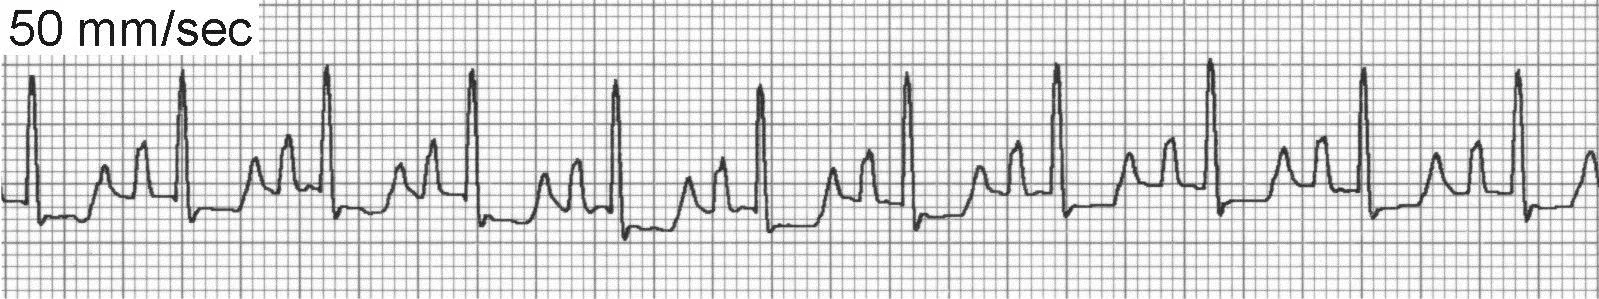

VT is defined as 3 or more ventricular premature complexes (VPCs) occurring in succession. VT produces wide and bizarre QRS complexes and displays a range of rate, morphology, and regularity; it is generally considered a serious and potentially life-threatening arrhythmia, especially in patients with underlying heart disease or clinical signs (weakness, collapse, shock). A variety of mechanisms can produce VT, including reentry, abnormal automaticity, and triggered activity. P waves may still be visible (Figure 2A) but there is no consistent temporal relationship with QRS complexes. SVT with abnormal ventricular conduction (eg, bundle branch block) can be confused with VT.

Unifocal VT is the most common type and (when sustained) produces a fast, regular cardiac rhythm.

Paroxysmal VT (Figure 2B) may produce irregular bursts of tachycardia that interrupt an otherwise normal rhythm.